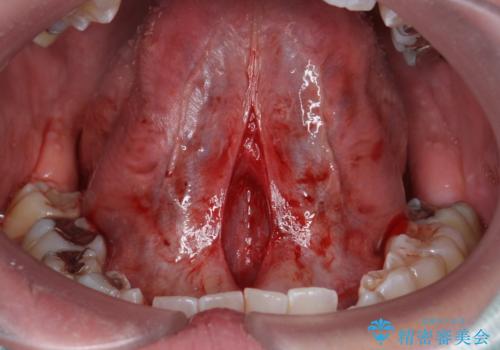

治癒も良好で、しゃべりやすくなったと大変喜んでいただけました。

この治療は、来院された当日での処置が可能です。